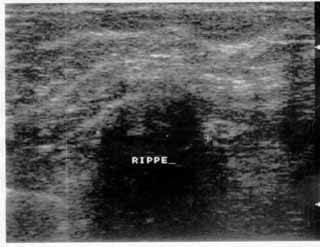

Η κλινικο-υπερηχογραφική διερεύνηση του μαστού είναι μία ακίνδυνη και πολύ αποτελεσματική μέθοδος εντόπισης εστιακών ευρημάτων.

Οι απεικονίσεις των περιστατικών που επιδεικνύονται παρακάτω, έγιναν με κυρτές κεφαλές 3,5 και 5 ΜΗΖ, προκειμένου να φανεί, ότι και με τον εξοπλισμό αυτό, που σιγά-σιγά διαθέτουν όλο και περισσότερα ιατρεία, είμαστε σε θέση να έχουμε ικανοποιητικά αποτελέσματα.

Oι τελευταίες 4 απεικονίσεις έγιναν με ειδικό για μαστό ηχοβολέα linear, εναλλασσομένης συχνότητος 7,5-10ΜΗΖ.